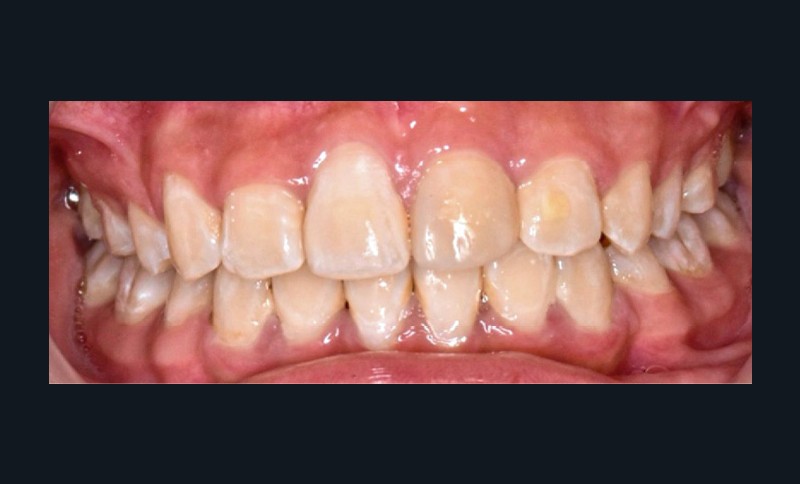

Une patiente âgée de 12 ans se présente en consultation, motivée par la position de son incisive centrale maxillaire, décrite comme « en avant », marquée par une dyschromie et une mobilité de grade 2 selon Muhlemann. L’examen clinique montre l’absence de 23 sur l’arcade, une dysharmonie dents-arcade marquée, un surplomb accentué, et une déviation des milieux inter-incisifs, conséquence du comblement spontané de l’espace de 23. L’ensemble s’inscrit dans un contexte de Classe I d’Angle molaire. L’orthopantomogramme révèle l’inclusion de 23, associée à une résorption radiculaire étendue aux deux tiers de 21. La 22 ne présente aucune altération visible.

La patiente, de profil normodivergent, présente une Classe I squelettique sans troubles fonctionnels (fig. 1-8).